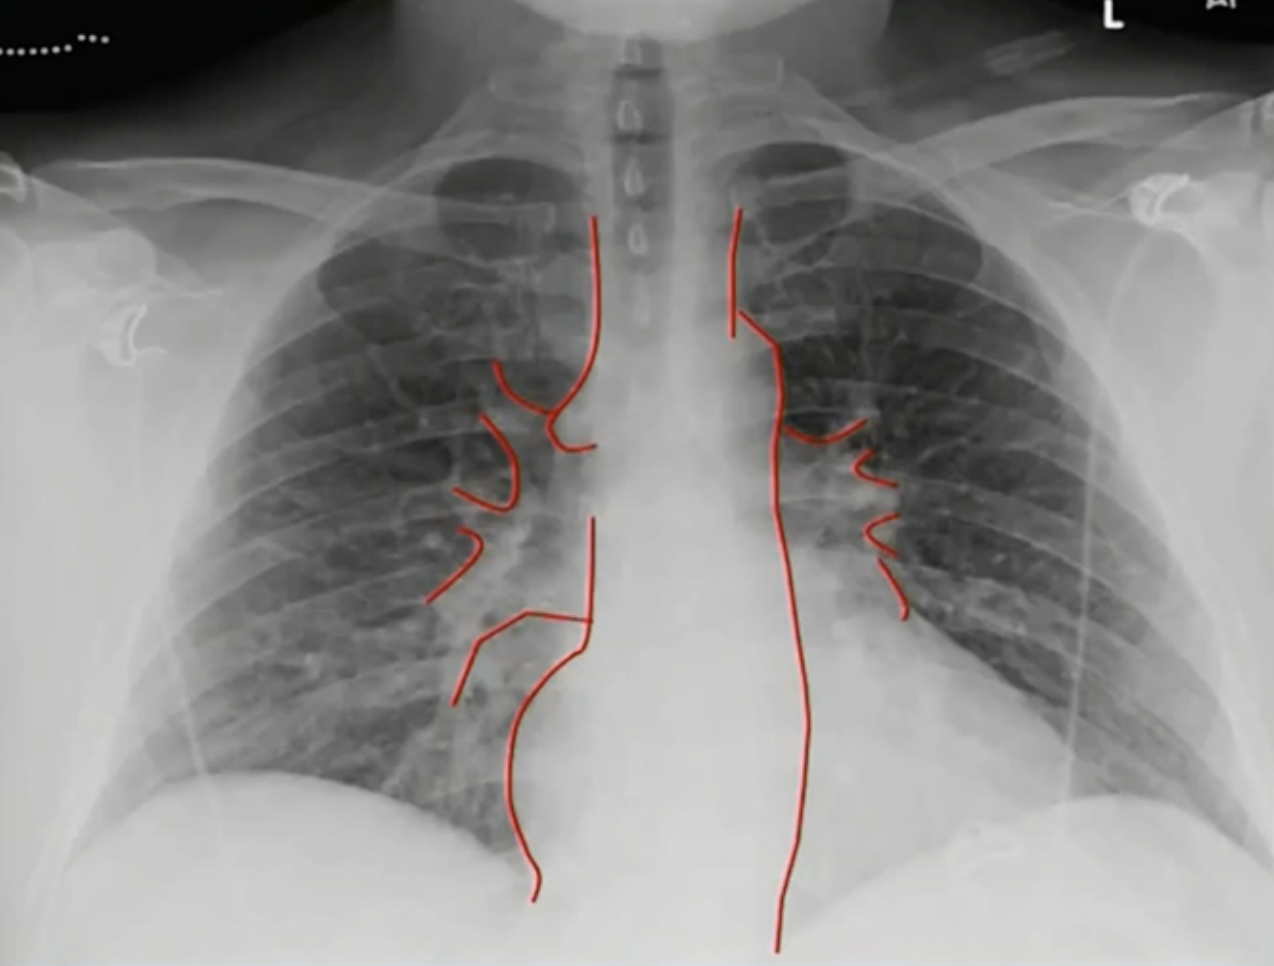

# 正位